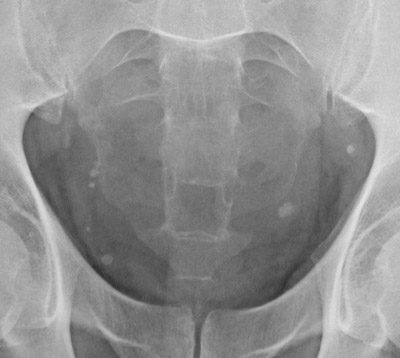

| This abdominal plain film reveals multiple small, discrete bright densities in the pelvis. These are phleboliths, or small calcifications that are a fairly common finding in middle-aged to older adults. Phleboliths have no significance, other than to distinguish them from other objects such as urinary tract calculi. A magnified view is seen below. |